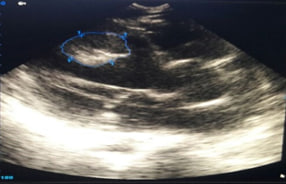

5 Pericardial effusion

The main task for bed echocardiography in a new coronavirus infection is to assess:

1. global and regional contractile function of the LV and right ventricle (RV) (qualitatively);

2. the size of the heart chambers (dilatation of the chambers);

3. the presence of fluid in the pericardial cavity and in the pleural cavities;

4. presence of mitral regurgitation (qualitatively);

5. the presence of additional formations in the cavities and structure of the heart (blood clots);

6. volemic status (diameter of the inferior vena cava);

7. Ultrasound profile of the lungs .

High-speed and temporary parameters of the high-amplitude reflected signals of the movement will help to reveal early dysfunction of a myocardium at that stage of its development when traditional EChOKG indicators don’t change yet. The high-speed indicators of the high-amplitude reflected movementsignals easily are registered by means of usual faltering wave doppler sonography in this connection the technique is available to broad diagnostic practice